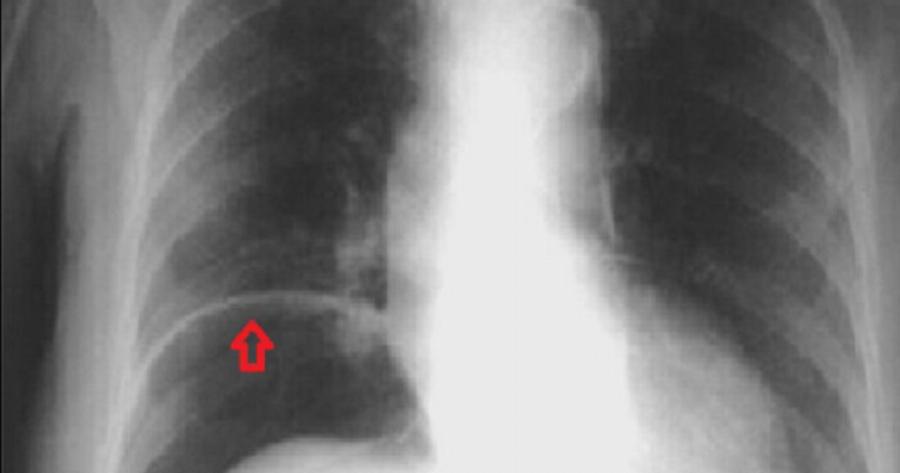

Δεν πίστευαν στα μάτια τους οι γιατροί νοσοκομείου στη Λιθουανία όταν έβγαλαν ακτινογραφία σε άνδρα που παραπονιόταν για πόνους στην κοιλιά – «Δεν έχουμε ποτέ δει ξανά κάτι παρόμοιο» Οι γιατροί ενός νοσοκομείου στη Λιθουανία ανακοίνωσαν την Παρασκευή (1/10) πως ανακάλυψαν στο στομάχι ενός άνδρα διάφορα μικρά μεταλλικά αντικείμενα, όπως βίδες και καρφιά, βάρους άνω του ενός κιλού.

Ο ασθενής εισήχθη στο νοσοκομείο της Κλαϊπέντα, στη Βαλτική, καθώς παραπονιόταν για οξείς πόνους στην κοιλιακή χώρα. Οι γιατροί του έκαναν ακτινογραφία και σύντομα ανακάλυψαν πως μέσα στο στομάχι του υπήρχαν διάφορα μεταλλικά αντικείμενα, ορισμένα εκ των οποίων είχαν μήκος έως και 10 εκατοστά, με αποτέλεσμα να κινδυνεύει η ζωή του.

«Κατά τη διάρκεια της επέμβασης διάρκειας 3 ωρών (…), όλα τα ξένα σώματα, ακόμα και τα μικρότερα, αφαιρέθηκαν από το στομάχι του ασθενούς», δήλωσε ο χειρουργός Σαρούνας Νταϊλιντένας. Το νοσοκομείο έδωσε στη δημοσιότητα μια φωτογραφία από τις βίδες και τα καρφιά που βρέθηκαν στο στομάχι του ασθενούς.

«Δεν έχουμε ποτέ δει ξανά κάτι παρόμοιο», είπε ο Αλγκίρντας Σλεπαβίτσιους, επικεφαλής χειρουργός στο νοσοκομείο της Κλαϊπέντα. Σύμφωνα με τον ίδιο, ο άνδρας άρχισε να καταπίνει μεταλλικά αντικείμενα τις τελευταίες εβδομάδες αφότου σταμάτησε να πίνει. Η κατάσταση της υγείας του είναι σταθερή, συμπλήρωσε ο γιατρός.